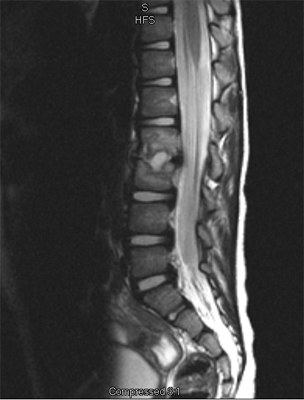

An MRI may be required if further examination of the spine is needed. An MRI machine uses magnetic waves, not X-rays, to show the soft tissues of the body. These tissues include the spinal cord, nerves, and discs. It can also evaluate spinal bones. An MRI allows your healthcare professional to look at slices of the area in question. The test may require the use of dye in an IV. Sedation or anesthesia may be needed to help your child lie still for this test.

Specific back pain means a structural cause for the pain is identifiable. Approximately 25 to 40 percent of children will have specific back pain and will show changes on imaging studies (such as X-ray or magnetic resonance images) that indicate a pathological reason (meaning one caused by disease) for their back pain. These causes include the following:

In the early stage of the injury an X-ray may not show a fracture. Special imaging tests such as magnetic resonance imaging (MRI), computed tomography scans (CT), or a bone scan may show signs of a stress fracture. Spondylolysis may cause pain in a particular spot in the low back and spasm of the muscles along the spine. Often it will cause pain into the buttocks or thighs. Spondylolysis will often heal with the appropriate rest, a change in activity levels, and by avoiding hyperextension and rotation of the spine. Bracing may be helpful if symptoms do not get better.